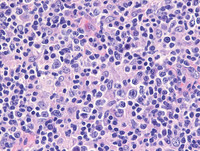

H&E images

Sections from the tonsil shows unremarkable surface epithelium with underlying lymphoid tissue demonstrating destruction of architecture with prominent interfollicular expansion by large clusters and sheets of reactive histiocytes with intervening areas demonstrating plasma cells and occasional immunoblasts. The follicular structures are otherwise morphologically compatible with reactive secondary follicles.